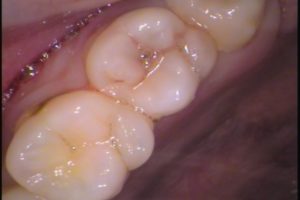

お口の中の状態は

左上奥歯7番目の歯です。

噛む面から口腔内カメラで撮影しています。

若干黒い感じがありますが、どこかわかりますか?